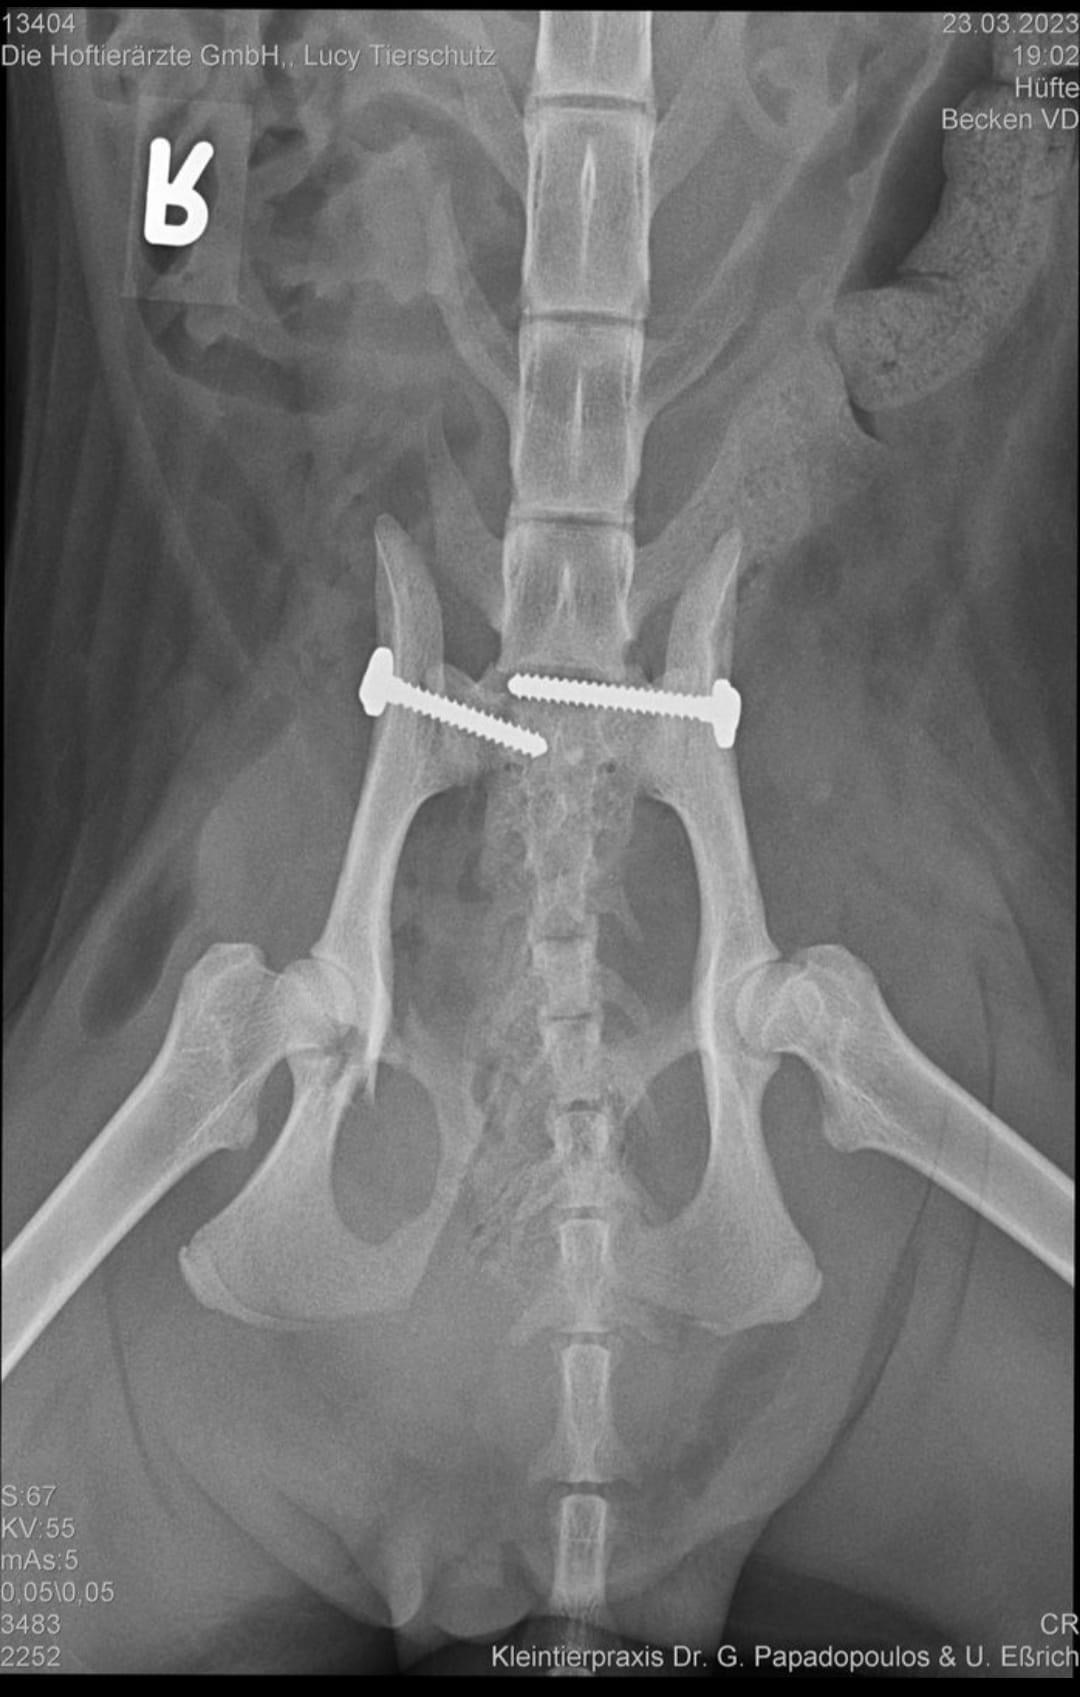

23.03.2023: Unsere Lucy hat die OP am frühen Abend gut überstanden. Es konnte alles so rekonstruiert werden, wie sich die Tierärzte das vorgestellt haben. Leider sind ihre Blutwerte nicht so berauschend und sie musste deswegen eine Bluttransfusion bekommen. Morgen wird dann entschieden ob sie zu uns zurück kann oder eventuell noch ein bis zwei Tage in der Praxis bleiben muss, bis sich die Blutwerte stabilisieren.

24.03.2023: Lucy ist zurück aus Berlin. Sie hat alles gut überstanden. Die OP war schon recht aufwendig. Die Tierärzte haben einiges geleistet an unserer Lucy. Beide Beckenknochen waren komplett ab und verschoben. Sie mussten wieder neu konstruiert und mit Schrauben fixiert werden. Sie hat noch einige Einblutungen in den Hinterbeinen, daher sind die Beine noch ziemlich angeschwollen. Das übernimmt ihr Körper aber wohl selbstständig und sollte sich in den nächsten Tagen geben. Sie bekommt jetzt in Ruhe ihre Medikamente und kann sich erholen.

30.04.2023: Der Termin für Lucy´s zweite OP steht jetzt fest. Am kommenden Mittwoch ist es soweit. Es wird dann ihr rechtes Hüftgelenk operiert. Die Tierärzte aus Berlin haben uns gesagt, dass sie darauf hoffen, das sich das Gelenk eventuell mit Bindegewebe festigen wird. Dem ist aber leider nicht so. Letzte Woche wurde ein neues Röntgenbild gemacht und da sieht man eindeutig, dass eine zweite OP notwendig ist.

03.05.2023: Die OP unserer Lucy ist gut verlaufen. Die Tierärzte in Wittstock und Berlin sind sehr zufrieden.

Am ersten Abend bei uns nach dem Unfall hatte Lucy undefinierbare Krämpfe, verbunden mit heftigen Blutungen. Da stand die Befürchtung im Raum, dass sie bedingt durch ihren Unfall gerade eine Fehlgeburt hatte. Das bestätigten uns heute auch die Tierärzte. Ihre Gebärmutter war daher ziemlich verklebt und wurde heute mit entfernt. Lucy´s Hüftgelenk wurde jetzt so rekonstruiert, dass sie nach der Genesung wieder ganz normal laufen können sollte.